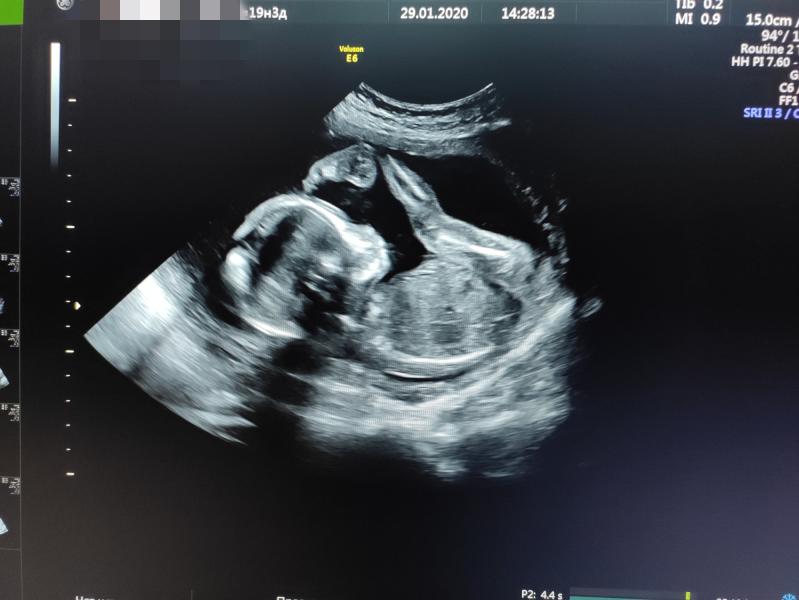

Второй скрининг. 17 роддом (800-летия Москвы)

Кто кого видит?)

Тоже фотогеничная поза) кто там?)

Вот это кадр! Гимнаст! Фото крутое)))

Ага, этож надо так загнуться ;)